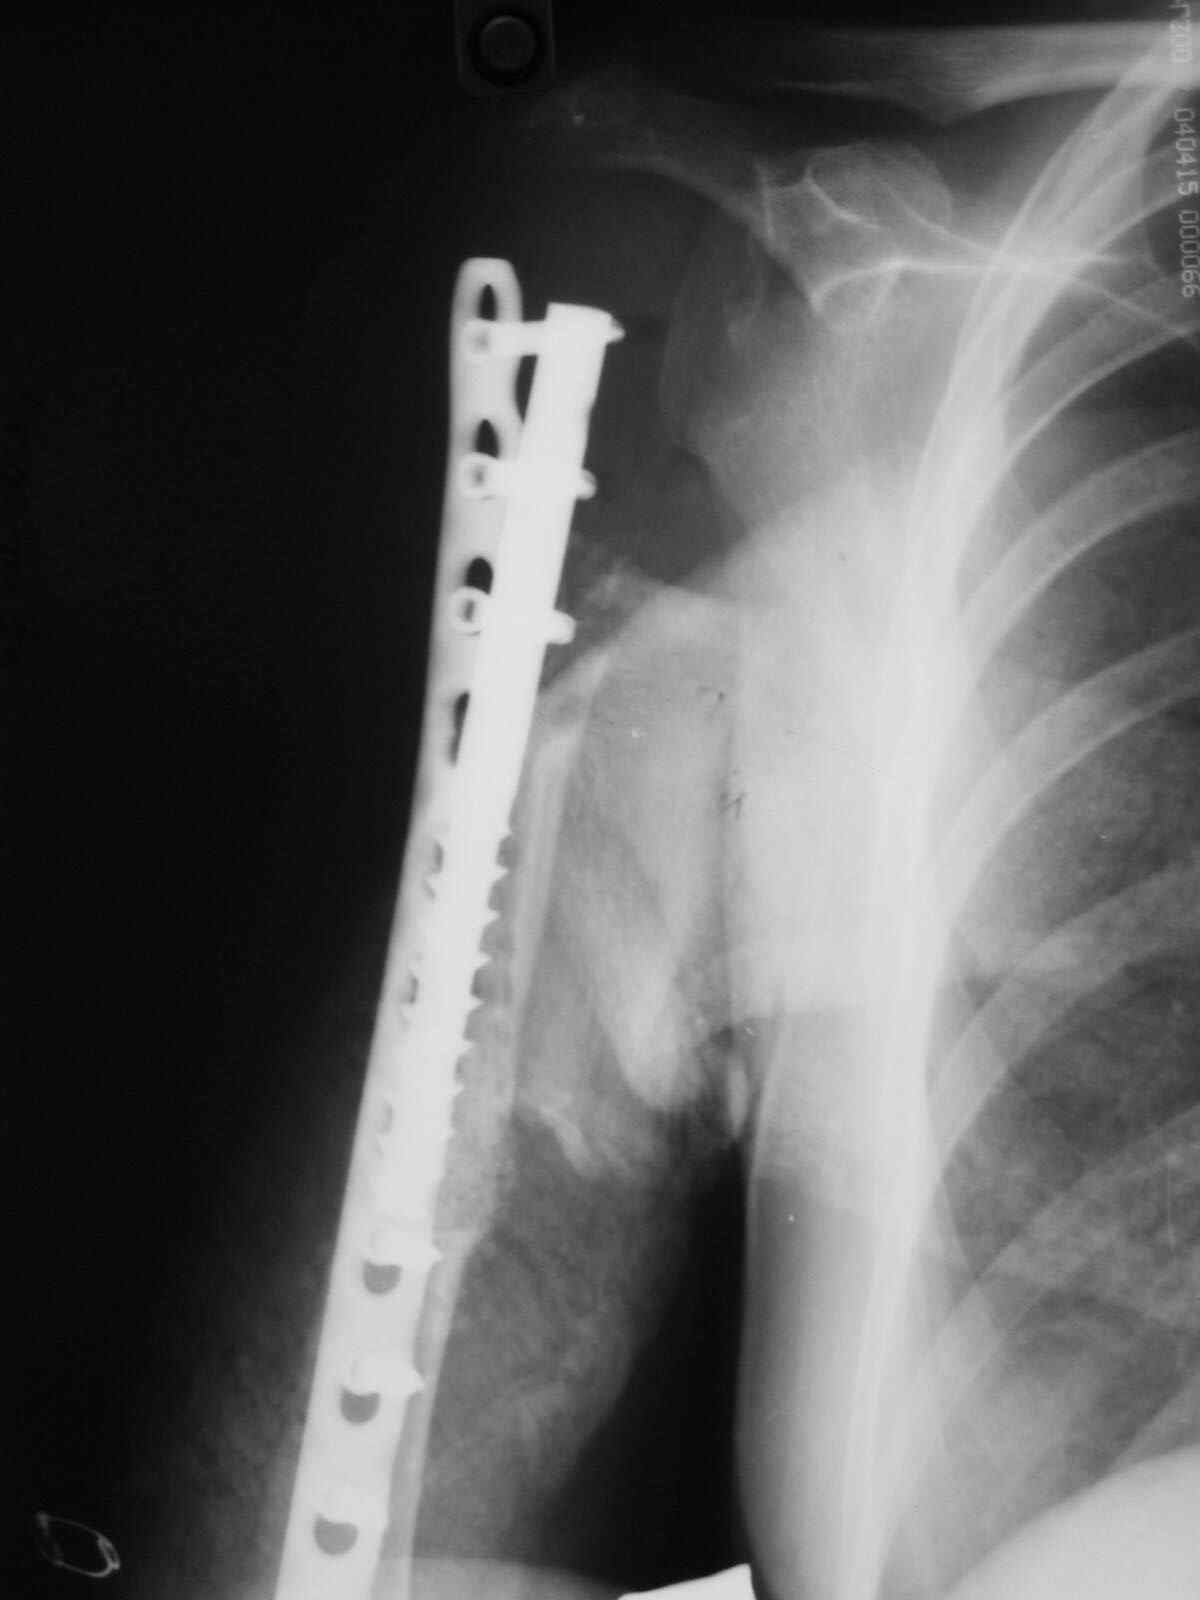

Выполнена операция- малоинвазивно проведена LCP пластина в образованный канал над

головкой протеза, фиксирована к протезу и дистально к плечевой кости, на зоной резорбции

трепонирована кость, удалена соединительно-тканная оболочка, полость заполнена

chronOS. П/о период без осложнений, клиника нестабильности купирована. Прошло 2 года по

телефону сообщила, что у нее все хорошо, продолжает жить счастливой жизнью сельской

труженицы